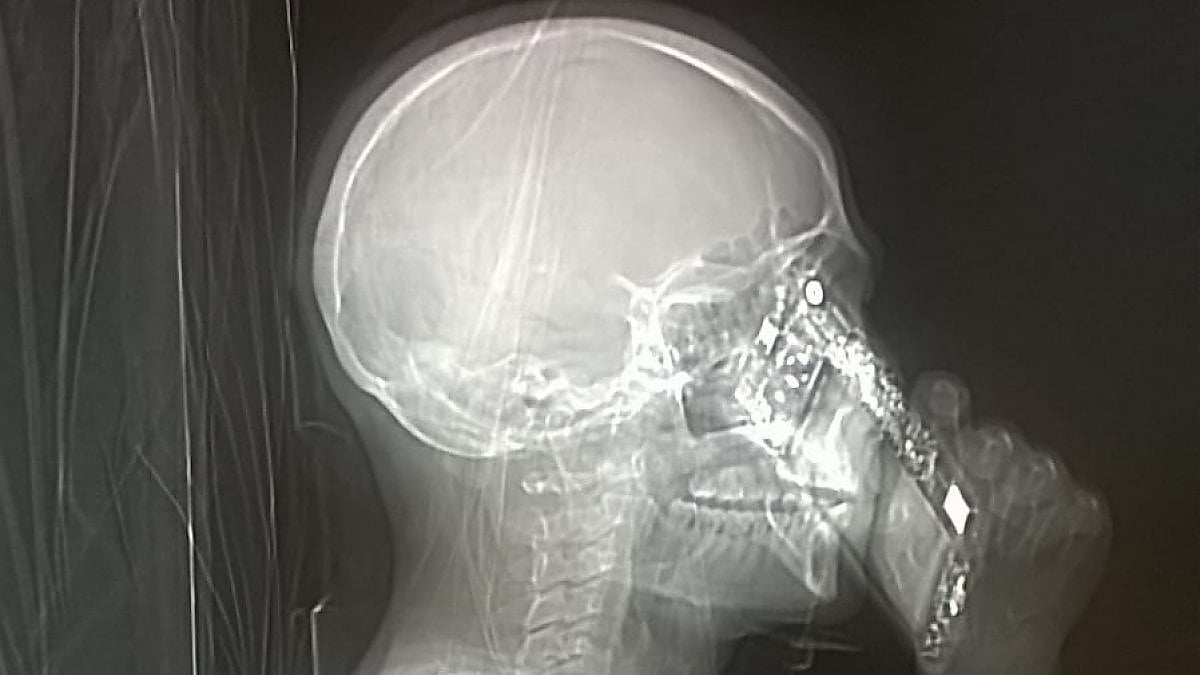

Sconcerto a Napoli per un episodio avvenuto all’ospedale Cardarelli. Una signora si era recata in fretta e furia nel noto nosocomio partenopeo, lamentando un forte mal di testa. I medici, allora, avevano deciso di sottoporla a una Tac per scoprire il motivo del suo patimento. Una volta arrivata nel reparto di neuroradiologia e messa dinanzi all’apparecchiatura per eseguire la Tac, la signora campana non ha saputo resistere ed ha risposto al cellulare.

Teschio e cellulare

Tecnici e medici dell’ospedale Cardarelli sono rimasti allibiti nel momento dello scatto della foto. L’immagine mostrava non solo il teschio ma anche un cellulare. La signora aveva violato il regolamento che proibisce di sottoporsi a tale esame con il cellulare indosso.

La donna di Napoli non solo avrebbe portato con sé lo smartphone durante la Tac ma avrebbe anche risposto a una chiamata. I medici, sconcertati, non hanno potuto fare altro che scattare e pubblicare la foto che ritrae la signora al cellulare. Lo scatto è diventato virale.

Un episodio paradossale per Mario Muto

‘L’avevo portato con me per sbaglio’, avrebbe detto la donna al personale sanitario, tentando di discolparsi. Il fatto, per il primario del reparto di neuroradiologia, Mario Muto, è semplicemente paradossale. Per la cronaca, la signora è stata sottoposta a una seconda Tac (senza smartphone) da cui non sono emerse particolari malattie. La donna è sana ma deve ricordarsi che smartphone e apparecchi elettronici non vanno assolutamente introdotti nei macchinari per eseguire la Tac.